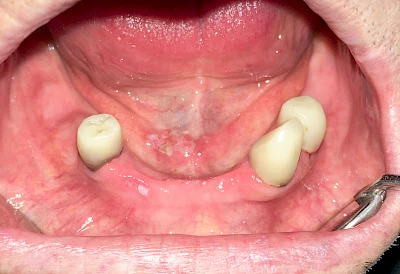

Einzündungen der kleinen Speicheldrüsen im Gaumen fallen dagegen durch kleine punktförmige Rötungen auf. Wenn ausreichende Flüssigkeitszufuhr und ggf. sanftes Massieren der Speicheldrüsen und der Ausführungsgänge (z. B. Parotitisprophylaxe) keine Verbesserung erzielen lassen oder wenn zusätzliche Symptome wie z. B. Fieber auftreten, sollte ein Arzt oder Zahnarzt hinzugezogen werden.